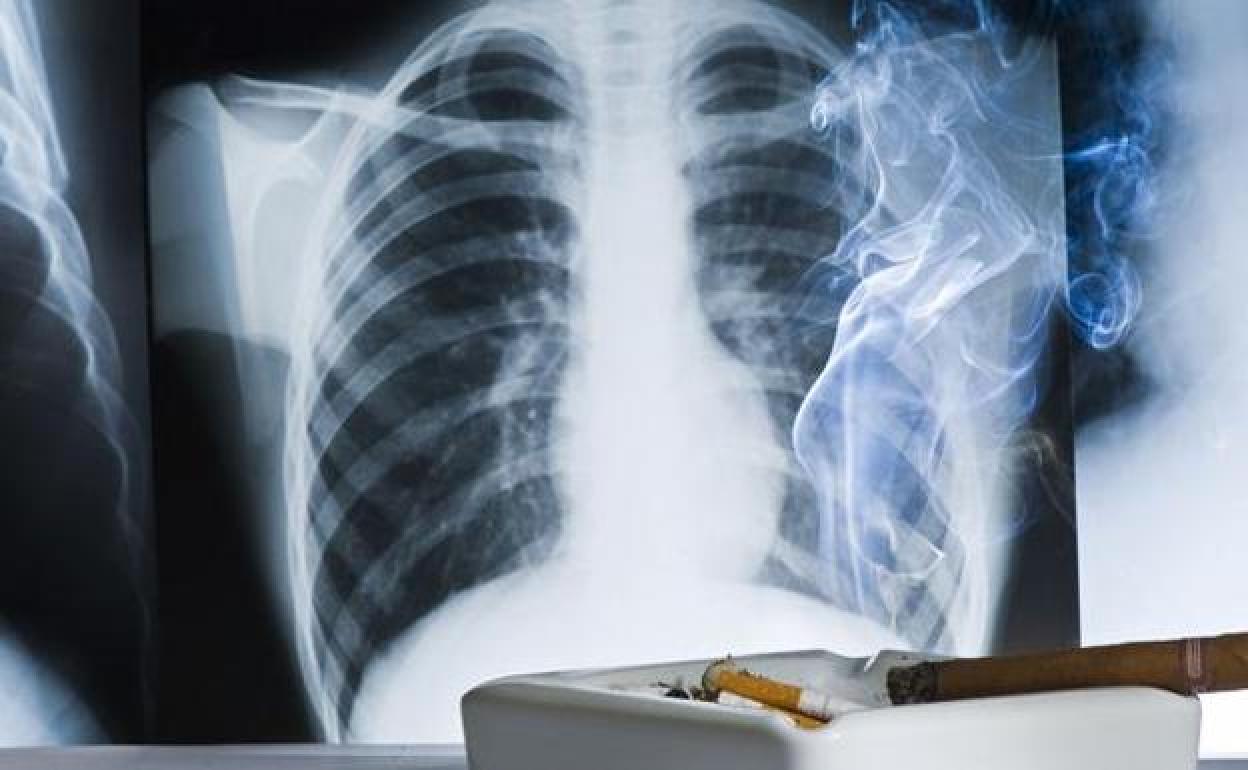

El cáncer de pulmón es uno de los más frecuentes y agresivos. R. C./Vídeo: Atlas

Investigadores pertenecientes al Grupo Español de Cáncer de Pulmón (GECP) han ratificado un cambio en el abordaje de estos tumores (siempre en estadios iniciales y sin metástasis) con una estrategia terapéutica que aumenta hasta el 93% (antes era el 69%) los pacientes candidatos a cirugía y logra erradicar el tumor en casi el 37% de los casos. El estudio, que observó a 86 pacientes procedentes de veinte hospitales españoles, se presentará el 5 de junio en el congreso de la Sociedad Americana de Oncología (ASCO) bajo el nombre de NADIM II. La investigación corrobora los beneficios de tratar los tumores de pulmón (el de mayor tasa de mortalidad en nuestro país) con quimio-inmunoterapia antes de someterlos a una cirugía, lo que ya se apuntaba en otro estudio anterior del GECP, en 2019.

El cáncer de pulmón se cobra la vida de unas 25.000 personas en España, lo que lo convierte en el tumor con mayor tasa de mortalidad. Junto a los de hígado, páncreas y esófago, se trata del que peor pronóstico presenta y junto al colorrectal, el de próstata y el de mama, es el más frecuente, con 30.000 nuevos casos diagnosticados al año.